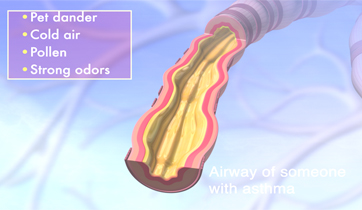

Asthma and its Triggers

Singulair, Merck

Rapp Collins Worldwide

New version in 2012 for UCSF

Patient education animation explaining Asthma and its triggers. The resulting constriction of the airways and the build up of mucus is explained, followed by tactics to maintain airflow and avoid attacks.